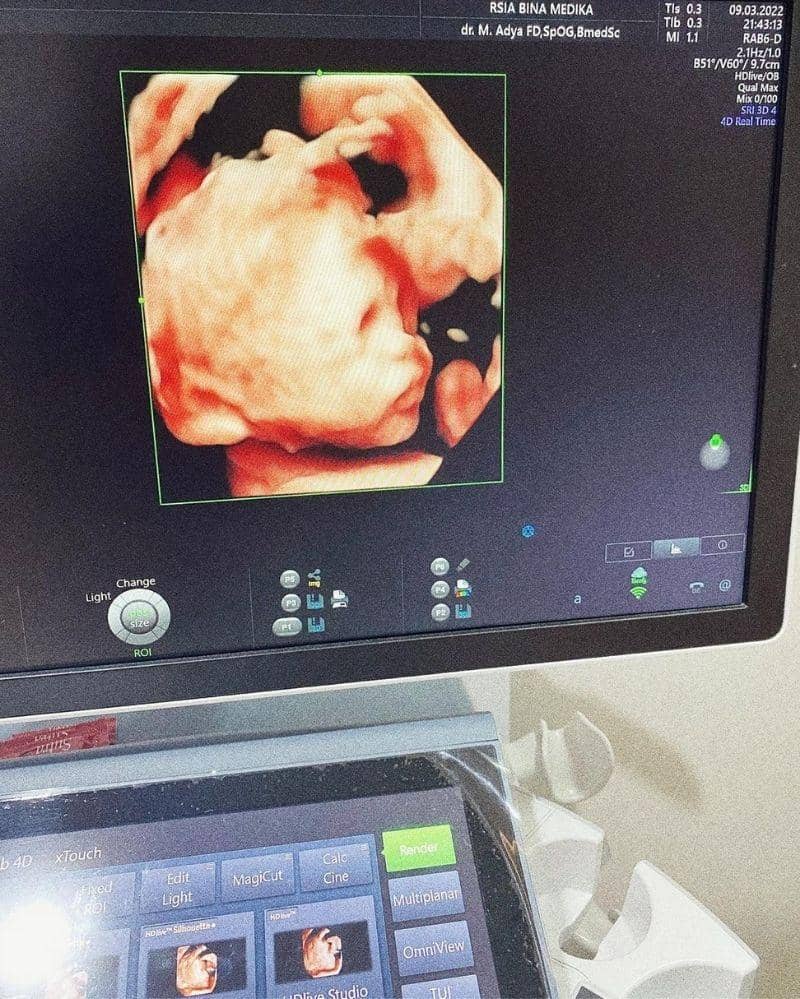

Pasangan Bunga Jelitha dan Syamsir Alam kini sedang diselimuti kebahagiaan. Pasalnya, Bunga Jelitha kini sedang mengandung anak keduanya, setelah sebelumnya melahirkan anak pertamanya pada Januari 2021.

Bunga Jelitha mengumumkan kabar bahagia ini lewat unggahan di Instagramnya pada 2 Desember 2021 lalu. Unggahannya tersebut sontak dibanjiri ucapan selamat dari kerabat dan warganet.

Sudah memasuki kehamilan 4 bulan, Bunga Jelitha mengaku belum menyiapkan nama untuk calon bayi di kandungannya. Alhasil, Bunga menyebutnya dengan panggilan "dedek". Sedangkan saat hamil Akleema, Bunga sudah menentukan namanya sejak kehamilan 4 bulan.

Selain itu, ia juga belum mengungkapkan jenis kelamin sang bayi dan meminta warganet untuk menebaknya.

"By the way, dedek belum ada nama. Waktu Akleema, pas 4 bulan udah nyiapin nama dan udah bisa nyebut Baby A. Hayo tebak dedek boy/girl?," tulis Bunga Jelitha.

Walaupun belum mengungkapkan jenis kelamin calon bayinya, namun Bunga Jelitha sudah mengungkapkan hari perkiraan lahir. Model yang juga mewakili Indonesia di ajang Miss Universe 2017 ini diperkirakan akan melahirkan pada akhir Juni atau awal Juli 2022.

Namun, Bunga berharap ia bisa melahirkan di tanggal 6 Juli 2022. Alasannya karena tanggal tersebut bersamaan dengan hari ulang tahun Syamsir Alam.